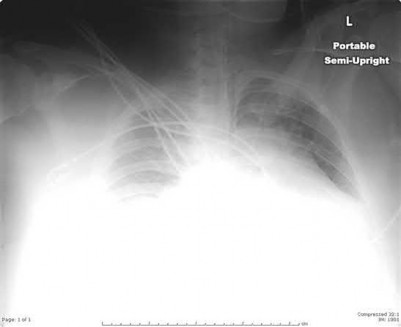

All of the following are factors associated with transfer of patients to Level 1 trauma centers EXCEPT:

Caucasian race has not been found to be a predictor for transfer to a Level 1 trauma center.

The retrospective case-control study by Koval et al found that African-American race, presence of medical comorbidity, medicaid insurance, and male gender are predictors for transfer of patients to a trauma center that have ISS scores less than 9.

The article by Nathens et al found that lack of insurance was an independent predictor for transfer to a trauma center after adjusting for differences in injury severity. An injury severity score of 36 represents a patient that has sustained life-threatening polytrauma and should be transferred to a Level 1 trauma center.